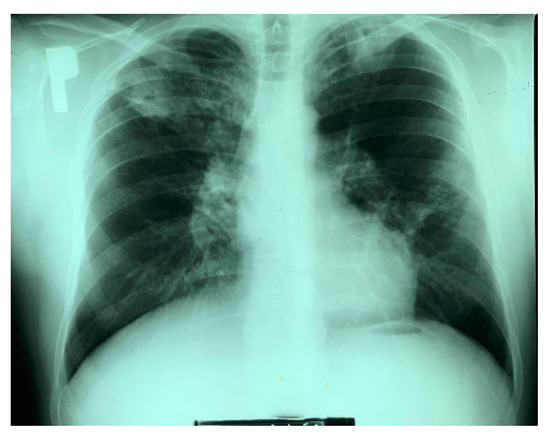

3.1. Human Case